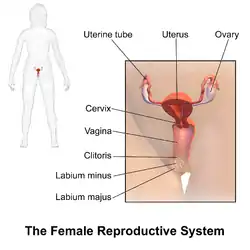

The female reproductive system is made up of the internal and external sex organs that function in the reproduction of new offspring. In humans, the female reproductive system is immature at birth and develops to maturity at puberty to be able to produce gametes, and to carry a fetus to full term. The internal sex organs are the vagina, uterus, fallopian tubes, and ovaries. The female reproductive tract includes the vagina, uterus, and fallopian tubes and is prone to infections.[1] The vagina allows for sexual intercourse and childbirth, and is connected to the uterus at the cervix. The uterus or womb accommodates the embryo which develops into the fetus. The uterus also produces secretions which help the transit of sperm to the fallopian tubes, where sperm fertilize ova (egg cells) produced by the ovaries. The external sex organs are also known as the genitals and these are the organs of the vulva including the labia, clitoris, and vaginal opening.[2]

The vulva is of all of the external parts and tissues and includes the following:[3]

- Clitoris: an organ located at the top of the vulva. It consists of the clitoral body and its pea-shaped glans that is protected by the clitoral hood. It also has two crus, two corpora cavernosa and two vestibular bulbs, which are erectile tissues that aid in clitoral erection as a part of sexual arousal by filling with blood.

- Labia: two types of vertical folds of skin called the labia majora (thick and large outer folds that protect other parts of the vulva) and the labia minora (thin and small inner folds that protect the vestibule from dryness, infections and irritation).

Vagina

Cervix

Uterus

Fallopian tubes

Ovaries